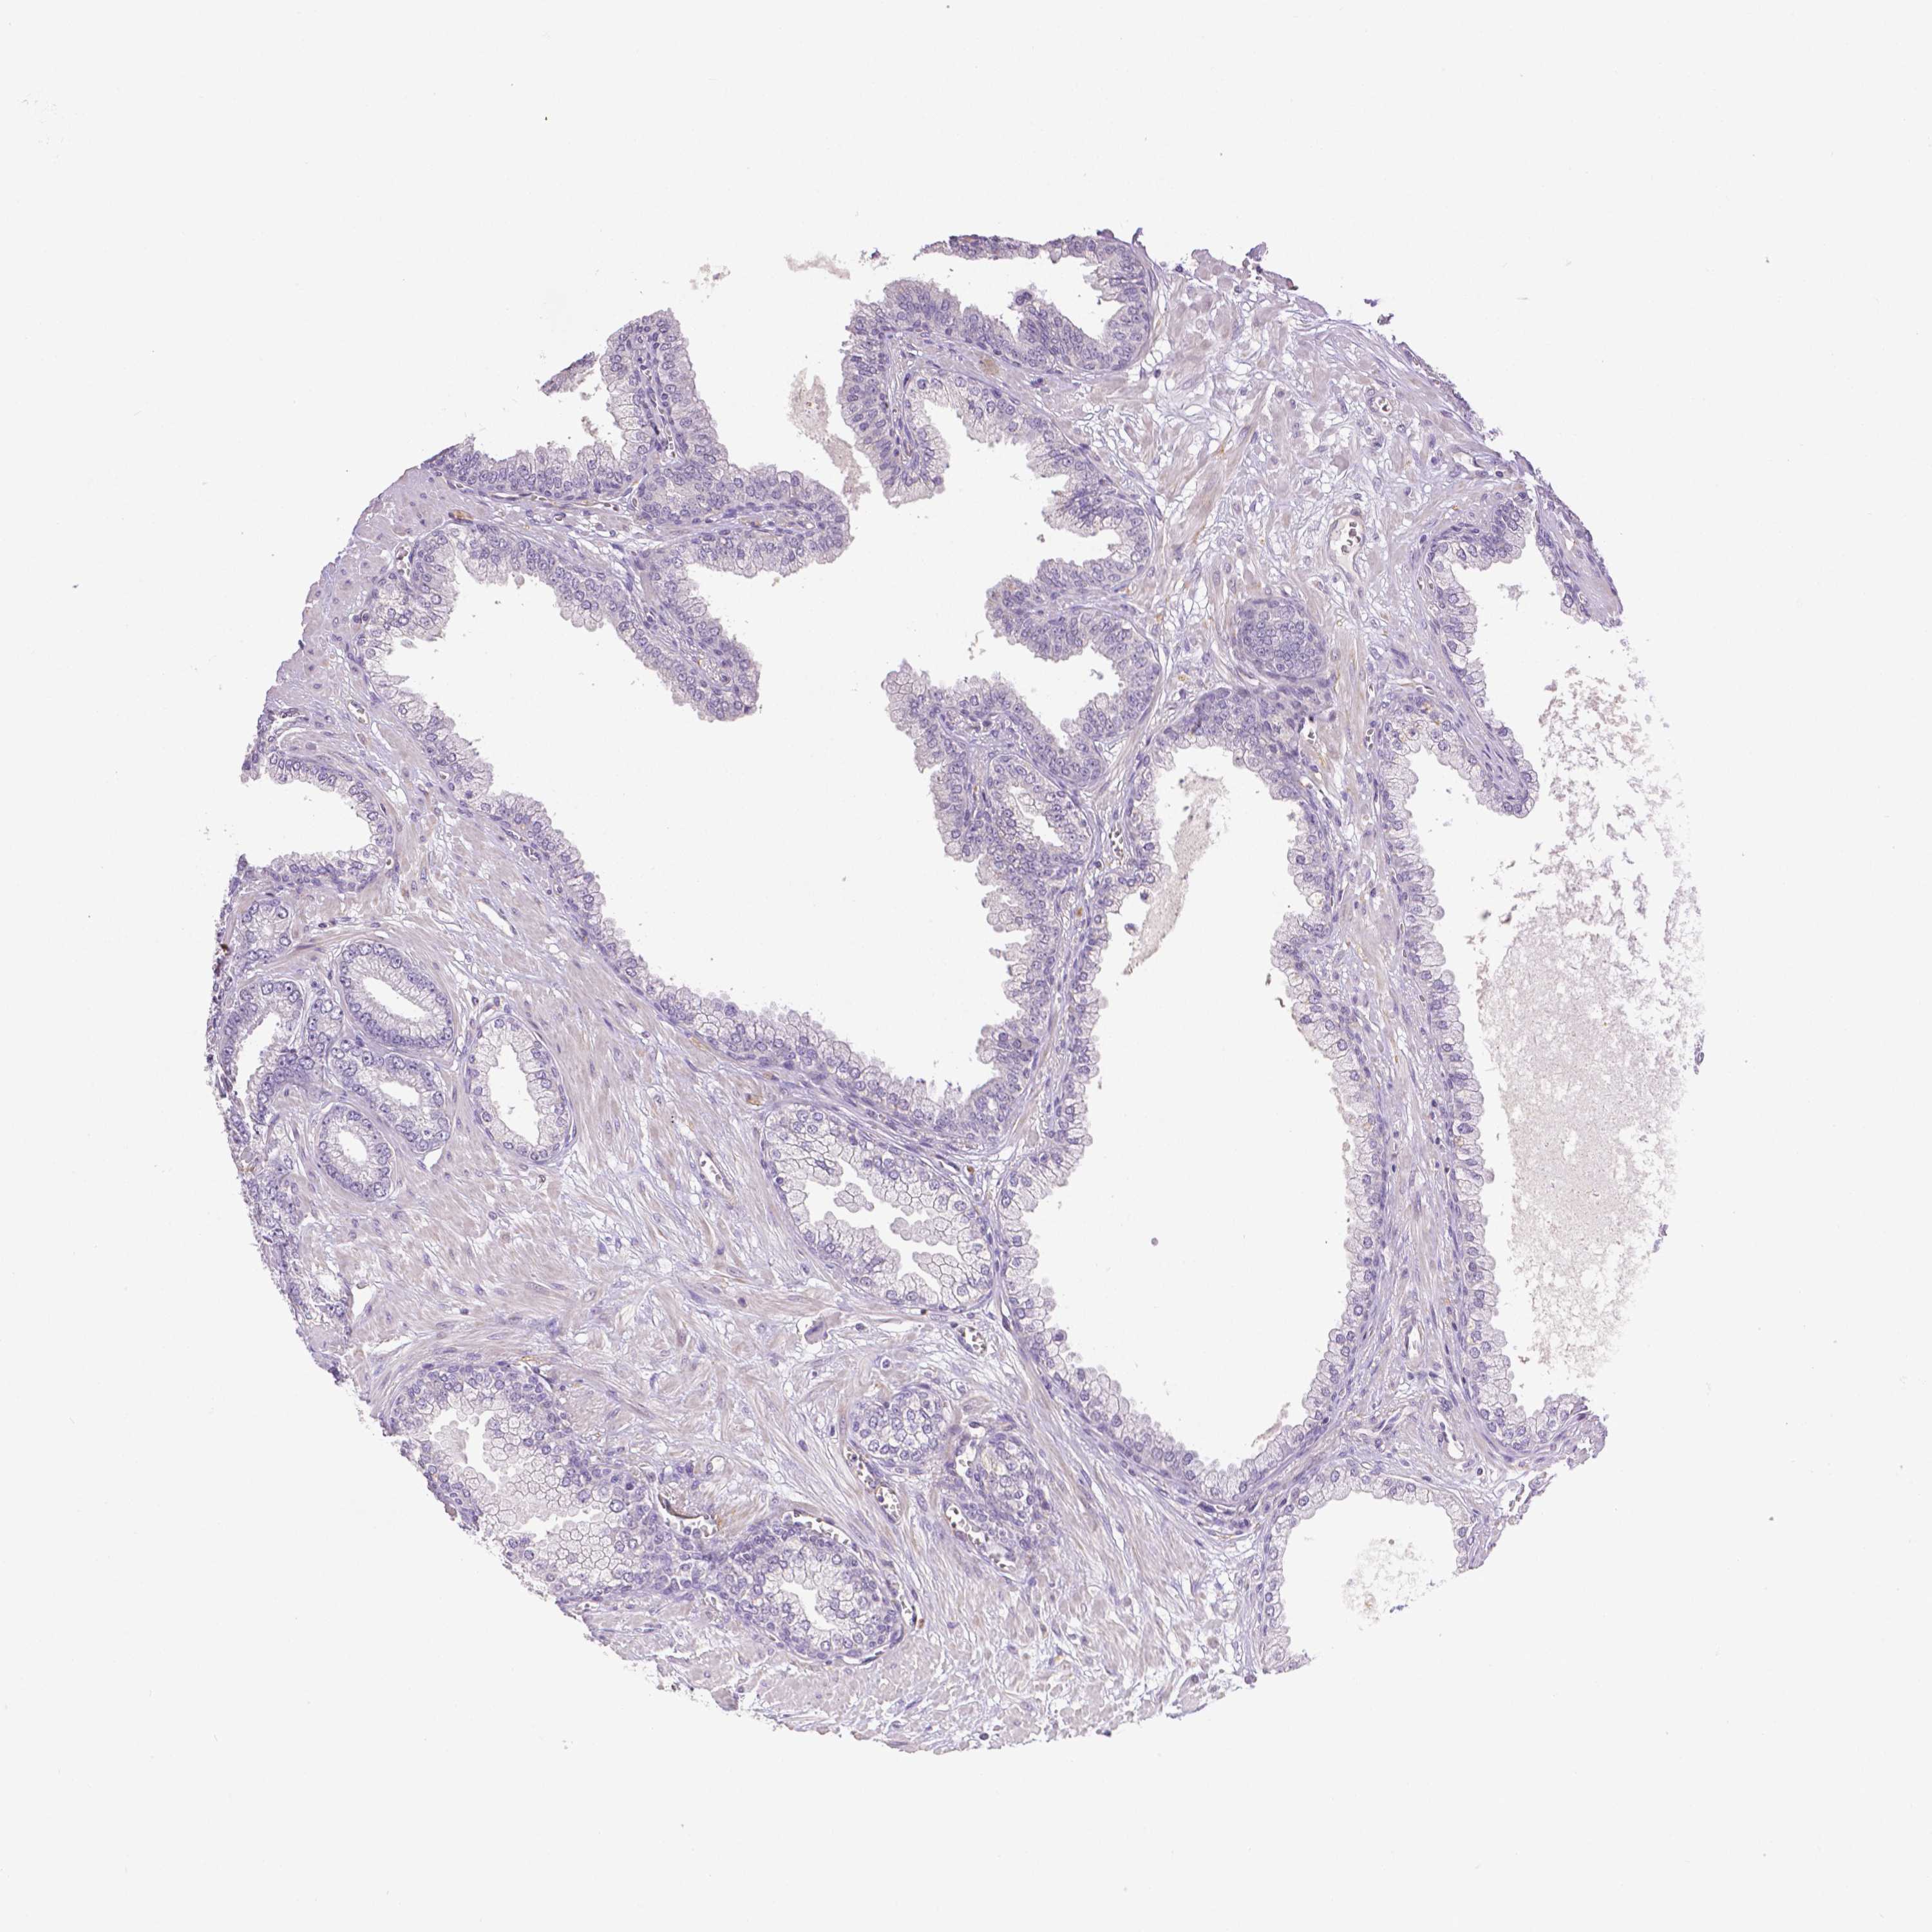

PROSTATE CANCER - Protein expressioni

A mouse-over function shows sample information and annotation data. Click on an image to view it in a full screen mode. Samples can be filtered based on level of antibody staining by selecting one or several of the following categories: high, medium, low and not detected. The assay and annotation is described here.

Antibody stainingi

Antibody staining in the annotated cell types in the current human tissue is reported as not detected, low, medium, or high, based on conventional immunohistochemistry profiling in selected tissues. This score is based on the combination of the staining intensity and fraction of stained cells.

Each image is clickable and will lead to virtual microscopy that enables deeper exploration of all samples and also displays staining intensity scores, fraction scores and subcellular localization as well as patient and tissue information for each sample.

Antibody CAB068243

Adenocarcinoma, High grade

Adenocarcinoma, NOS

Adenocarcinoma, Low grade